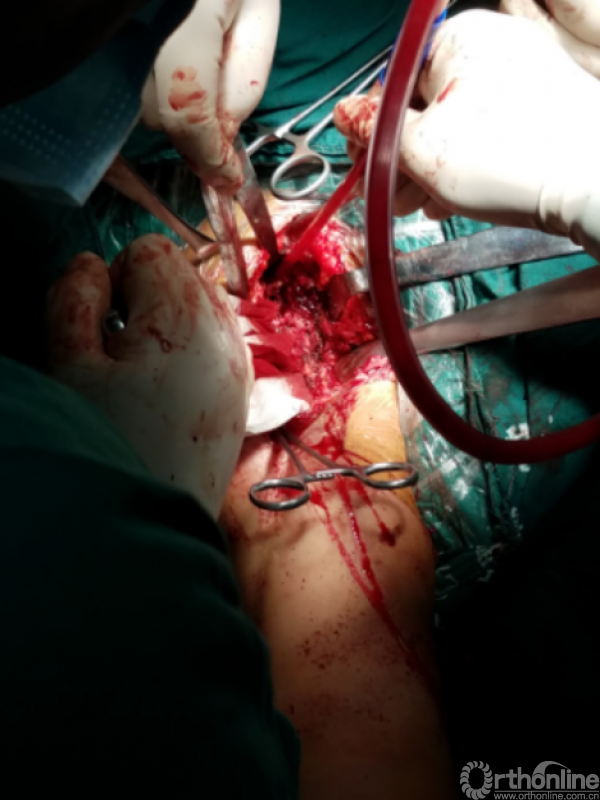

注意事项: 肱骨头内移至喙突处,位于后内侧下方已有骨桥连接

特别小心腋鞘及臂丛神经

提示无法顺利脱位!!!

小心咬出间隙后,牵引肘关节前屈肩关节后伸外旋,拉钩撬拨脱位!!

关节盂正常结构消失,至喙突偏内侧部位,上方紧贴肩峰下,仍然有骨质可用!

咬除连接骨桥,清理髓腔,恢复活动度

安尔碘溶液反复冲洗1000毫升,浸泡!!!

1.关节盂正常结构消失,前倾增大。

2.紧贴喙突内侧

3.骨质菲薄

4.特别小心肌皮神经及腋鞘

骨质疏松明显,皮质成虫蚀样改变,外侧缺损。